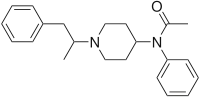

Anilidopiperidines

- 3-Allylfentanyl

- 3-Methylfentanyl

- 3-Methylthiofentanyl

- 4-Phenylfentanyl

- Alfentanil

- α-Methylacetylfentanyl

- α-Methylfentanyl

- α-Methylthiofentanyl

- Benzylfentanyl

- β-hydroxyfentanyl

- β-hydroxythiofentanyl

- β-Methylfentanyl

- Brifentanil

- Butyrfentanyl

- Carfentanil

- Fentanyl

- Lofentanil

- N-Methylcarfentanil

- Mirfentanil

- Ocfentanil

- Ohmefentanyl

- Parafluorofentanyl

- Phenaridine

- R-30490

- Remifentanil

- Sufentanil

- Thenylfentanyl

- Thiofentanyl

- Trefentanil

Structures